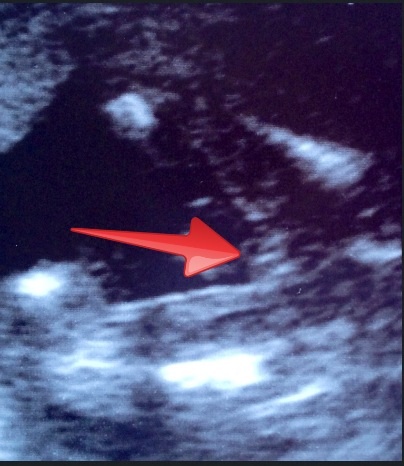

Edited!! I knew I could see a nub when I zoomed in... I have edited the pic to show it, where the red arrow is? What do you think?

Attachment 12596